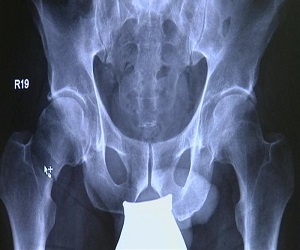

يعتبر كسر عنق أو مفصل الفخذ من الكسور الخطيرة جدا. وتعالج هذه الكسور مؤخرا في ألمانيا بعمليات دقيقة باستخدام حوض اصطناعي. إلا أن فترة ما بعد العملية طويلة نسبيا وخطيرة، إذ تنتج عنها التهابات وآلام مزمنة.

وفي ألمانيا يتم علاج كسر عنق الفخذ إما بتثبيت عنق الفخذ بواسطة مسامير أو بإجراء عملية جراحية يتم فيها زراعة عظم فخذ اصطناعي كامل. وبعد إجراء العلمية يتوجب على المريض الخضوع لعملية إعادة تأهيل. وهي فترة طويلة وخطيرة. إذ من الممكن أن يتعرض الشخص للإصابة بالتهاب في الرئة لعدم قدرة الدم على الحركة بشكل طبيعي في الرئة بسبب الاستلقاء لفترة طويلة، ما يؤدي إلى صعوبة في التنفس، حسب البروفسور راينهارد.